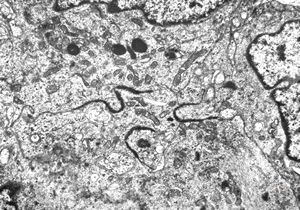

F,49y. | purulent meningitis- meningococcal v.s.

F,49y. | purulent meningitis- meningococcal v.s.

F,49y. | purulent meningitis- meningococcal v.s.